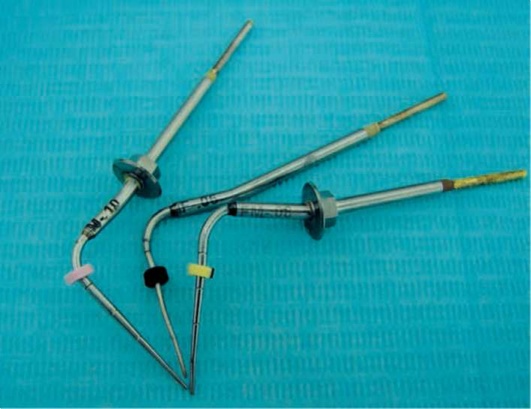

Протейперы. Инструменты для ручной обработки, позволяющие придать корневому каналу конусную форму за счет имеющихся агрессивных боковых граней, обладающих высокой режущей способностью. Удобная силиконовая ручка помогает увеличить эффективность расширения корневого канала (рис. 40-1).

pic 0330

Рис. 40-1. Набор протейперов для ручной обработки.